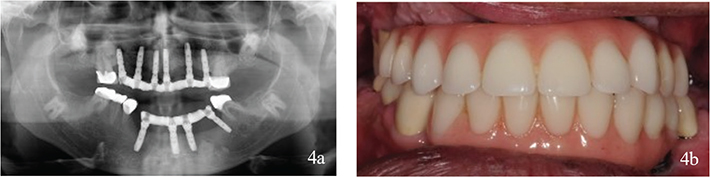

Figure 2

Figure 2. (a, b) Dental status after treatment abroad. Thirteen dental implants with a variety of designs and unfavourable placement had replaced teeth in both jaws. Interim prosthesis had been cemented on implant abutments and on teeth but was missing in the maxillae on examination. The molars in the mandibulae were restored with fixed dental prosthesis.

The prosthodontic work carried out for the patient was non-functional at this time.